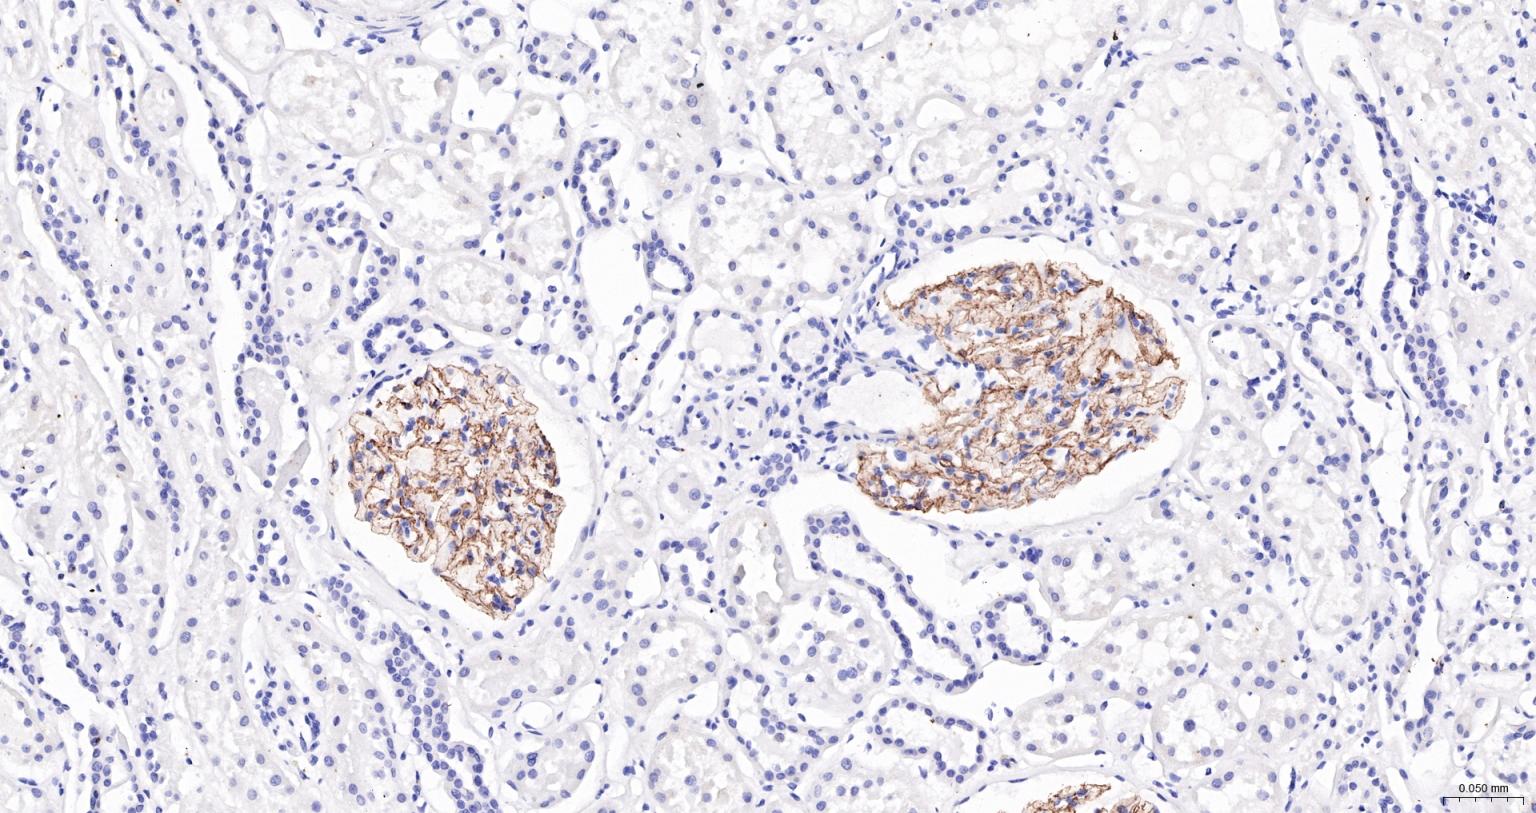

Nephrin Mouse mAb

肾小球细胞粘附分子受体单克隆抗体-bsm-43700M

IHC-PHuman1:100-500

Cell membrane; Single-pass type I membrane protein (Potential). Note=Predominantly located at podocyte slit diaphragm between podocyte foot processes. Also associated with podocyte apical plasma membrane.

Specifically expressed in podocytes of kidney glomeruli. Expressed in kidney glomeruli. In the embryo,expressed in the mesonephric kidney at E11 with strong expression in cranial tubules with podocyte-like structures. Expression is observed in the podocytes of the developing kidney from E13. High expression is also detected in the developing cerebellum, hindbrain, spinal cord, retina and hypothalamus. Expressed in skeletal muscle during myoblast fusion such as in the adult following acute injury and in the embryo but not detected in uninjured adult skeletal muscle. Isoform 1 and isoform 2 are expressed in the newborn brain and developing cerebellum. Isoform 1 is the predominant isoform in adult kidney.

Seems to play a role in the development or function of the kidney glomerular filtration barrier. Regulates glomerular vascular permeability. May anchor the podocyte slit diaphragm to the actin cytoskeleton. Plays a role in skeletal muscle formation through regulation of myoblast fusion.